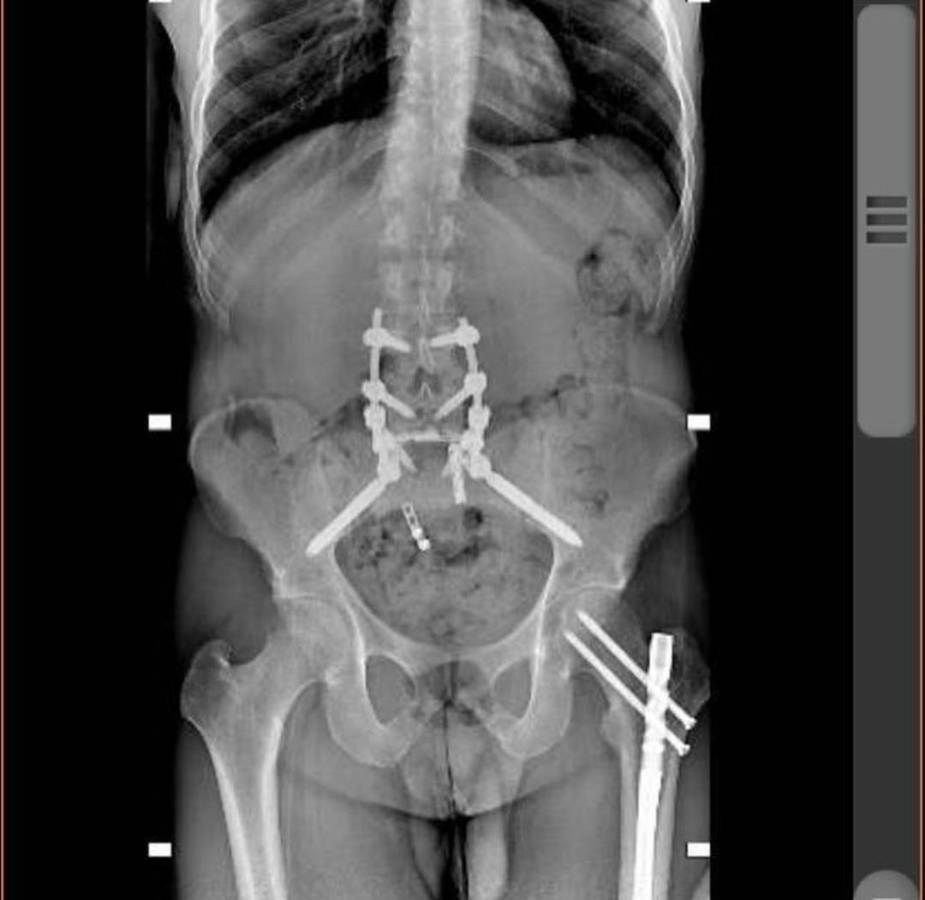

A través de su cuenta de Instagram, el joven compartió una serie de fotografías de los momentos más significativos tras el aparatoso incidente.

Michel relató que después de impactar contra el suelo a +100km/h, lo que más recuerda es que no podía mover el cuerpo desde el pecho hasta los pies.

“Después de una semana en Rhode Island, el doctor Ziya Gokaslan, todo su equipo y yo estábamos listos para ir al quirófano para arreglar lo que pudiera arreglarse. Cuando me abrieron la espalda solo me encontraron un nervio sacro roto. Fue entonces cuando las cosas dieron un giro drástico al convertir una cirugía de 16 horas en una cirugía de 6 horas y la noticia de que iba a poder caminar de nuevo”, narró.